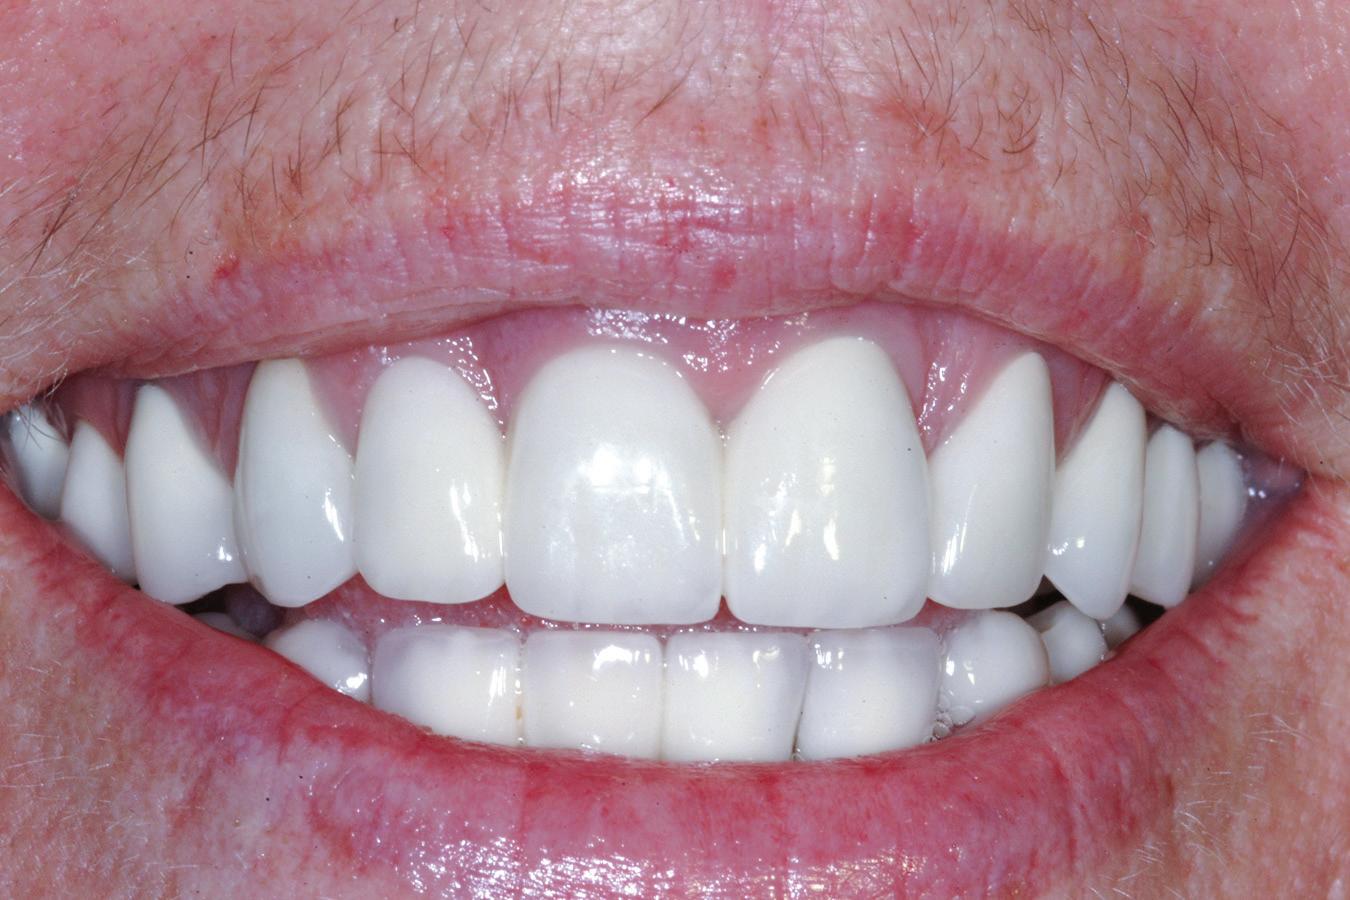

• Pacient cu restaurări deficitare pe dinți compromiși structural, tratamente endodontice eșuate, mobilitate avansată, pungi parodontale profunde, incisiv lateral absent congenital restaurat prin substituție canină inestetică, linie înaltă a zâmbetului. Rezolvarea? Colaborarea cu endodont, parodontolog, ortodont, protetician. Rezultatul? Succes clinic și satisfacția pacientului.

• Chirurgia implantară cu cea mai inteligentă planificare și mai precisă execuție va necesita în continuare un finisaj protetic care funcționează biomecanic și realizează o estetică naturală ideală individuală. Dacă există un aspect al tratamentului protetic cu provocări în era digitală, acesta ar consta în munca artistică minuțioasă a ceramistului, cu modelarea și pictarea dinților pentru a imita natura.

Colaborarea profesională și planificarea ghidată protetic sunt esențiale pentru rezultate predictibile de succes.